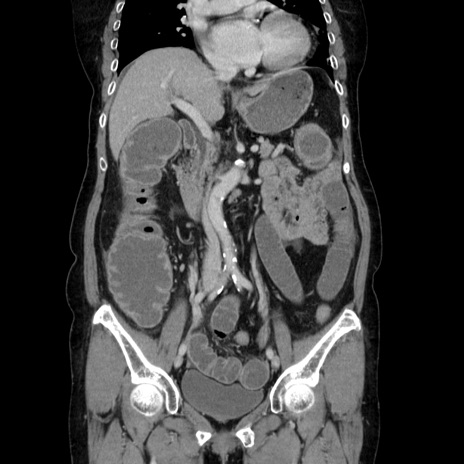

症例5(冠状断像)

【症例】70歳代女性

【主訴】お腹が張る

【現病歴】1週間くらい前から腹部膨満の自覚あり。昨日夜から増悪したため、本日救急外来受診。

【身体所見】意識清明、BT 36.5℃、BP 165/106mmHg、HR 80bpm、SpO2 98%、腹部:膨満、軟、自発痛・圧痛なし、触診にて不快感あり、腸蠕動音:減弱

【データ】WBC 12600、CRP 1.04

横断像